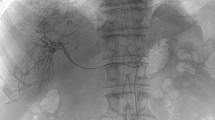

Short-course radiation therapy

A total of 32 mice (27 tumor-bearing mice and five healthy mice (positive controls)) received SCRT. Fifteen additional tumor-bearing mice (negative controls) did not receive SCRT. Before treatment, two 4 mm titanium fiducial markers (Horizon, Teleflex, Morrisville, NC, USA) were placed on opposing sides of the rectal tumor to aid in CT-guided SCRT targeting as described in Uccello et al.16. A small animal radiation research platform (SARRP, Xstrahl Inc., Suwanee, GA, USA) with a 5 mm collimator was used to irradiate mice in the treated group with 5 Gy (Gy) from day 9 to 13 post-tumor cell injection.

Shear wave elastography imaging

We used plane-wave single tracking location shear wave elastography (pSTL-SWE) on a commercially available ultrasound scanner (Vantage 256, Verasonics Inc., Kirkland, WA, USA) equipped with an 11-5v linear transducer array (Vantage 256, Verasonics Inc., Kirkland, WA, USA) to perform SWE18. Tumors were first located using a metal rod (1.35 mm diameter by 20 mm length) before acquiring three cross-sectional (~ 2 mm increments) SWE images. In addition, we used the bladder and the metal clips on both ends of the tumor to localize the tumor, as illustrated in (Supplementary Fig. 1). The tumor segmentation was performed in the ultrasound images. The cross-sectional area was computed for three acquired cross-sections, and the mean cross-sectional area was used as a surrogate of tumor volume. SWS and SWA values were computed using the time-of-flight18 and frequency shift19 methods. pSTL-SWE imaging was performed at three different times: before injecting tumor cells (day 0), during treatments (days 10 and 12 post-tumor cell injection), and post-SCRT (days 7, 9, 11, 14, and 16). We used ultrasound images to guide us as we manually segmented all tumor cross-sections. We calculated the mean SWS and SWA for each time point across all the segmented regions.